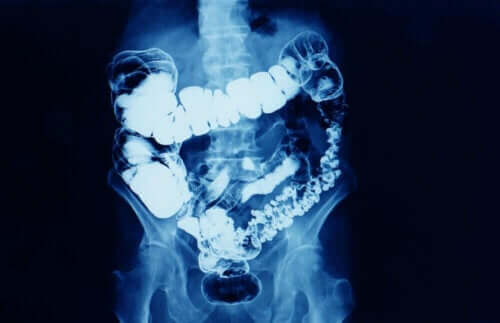

I allmänhet betyder förstoppning att avföringsfrekvensen är reducerad. Förstoppning är ett symtom som innebär att tarmtransiten av någon anledning har minskat. Förstoppning drabbar fler kvinnor än män, särskilt kvinnor mellan 20 och 35 år och efter 60 års ålder.

Beroende på hur länge det varar kan förstoppning delas in i två typer:

- Tillfällig förstoppning: detta kan bero på förändringar i kost och vattenintag, brist på motion, behandling med vissa mediciner eller stressiga situationer.

- Kronisk förstoppning: För att läkare ska diagnostisera förstoppning som kronisk måste den vara i minst tre månader.

Man kan också relatera kronisk förstoppning till situationer som liknar de vid tillfällig förstoppning, men som varar längre. Andra gånger beror det dock på matsmältningsproblem och vissa sjukdomar.